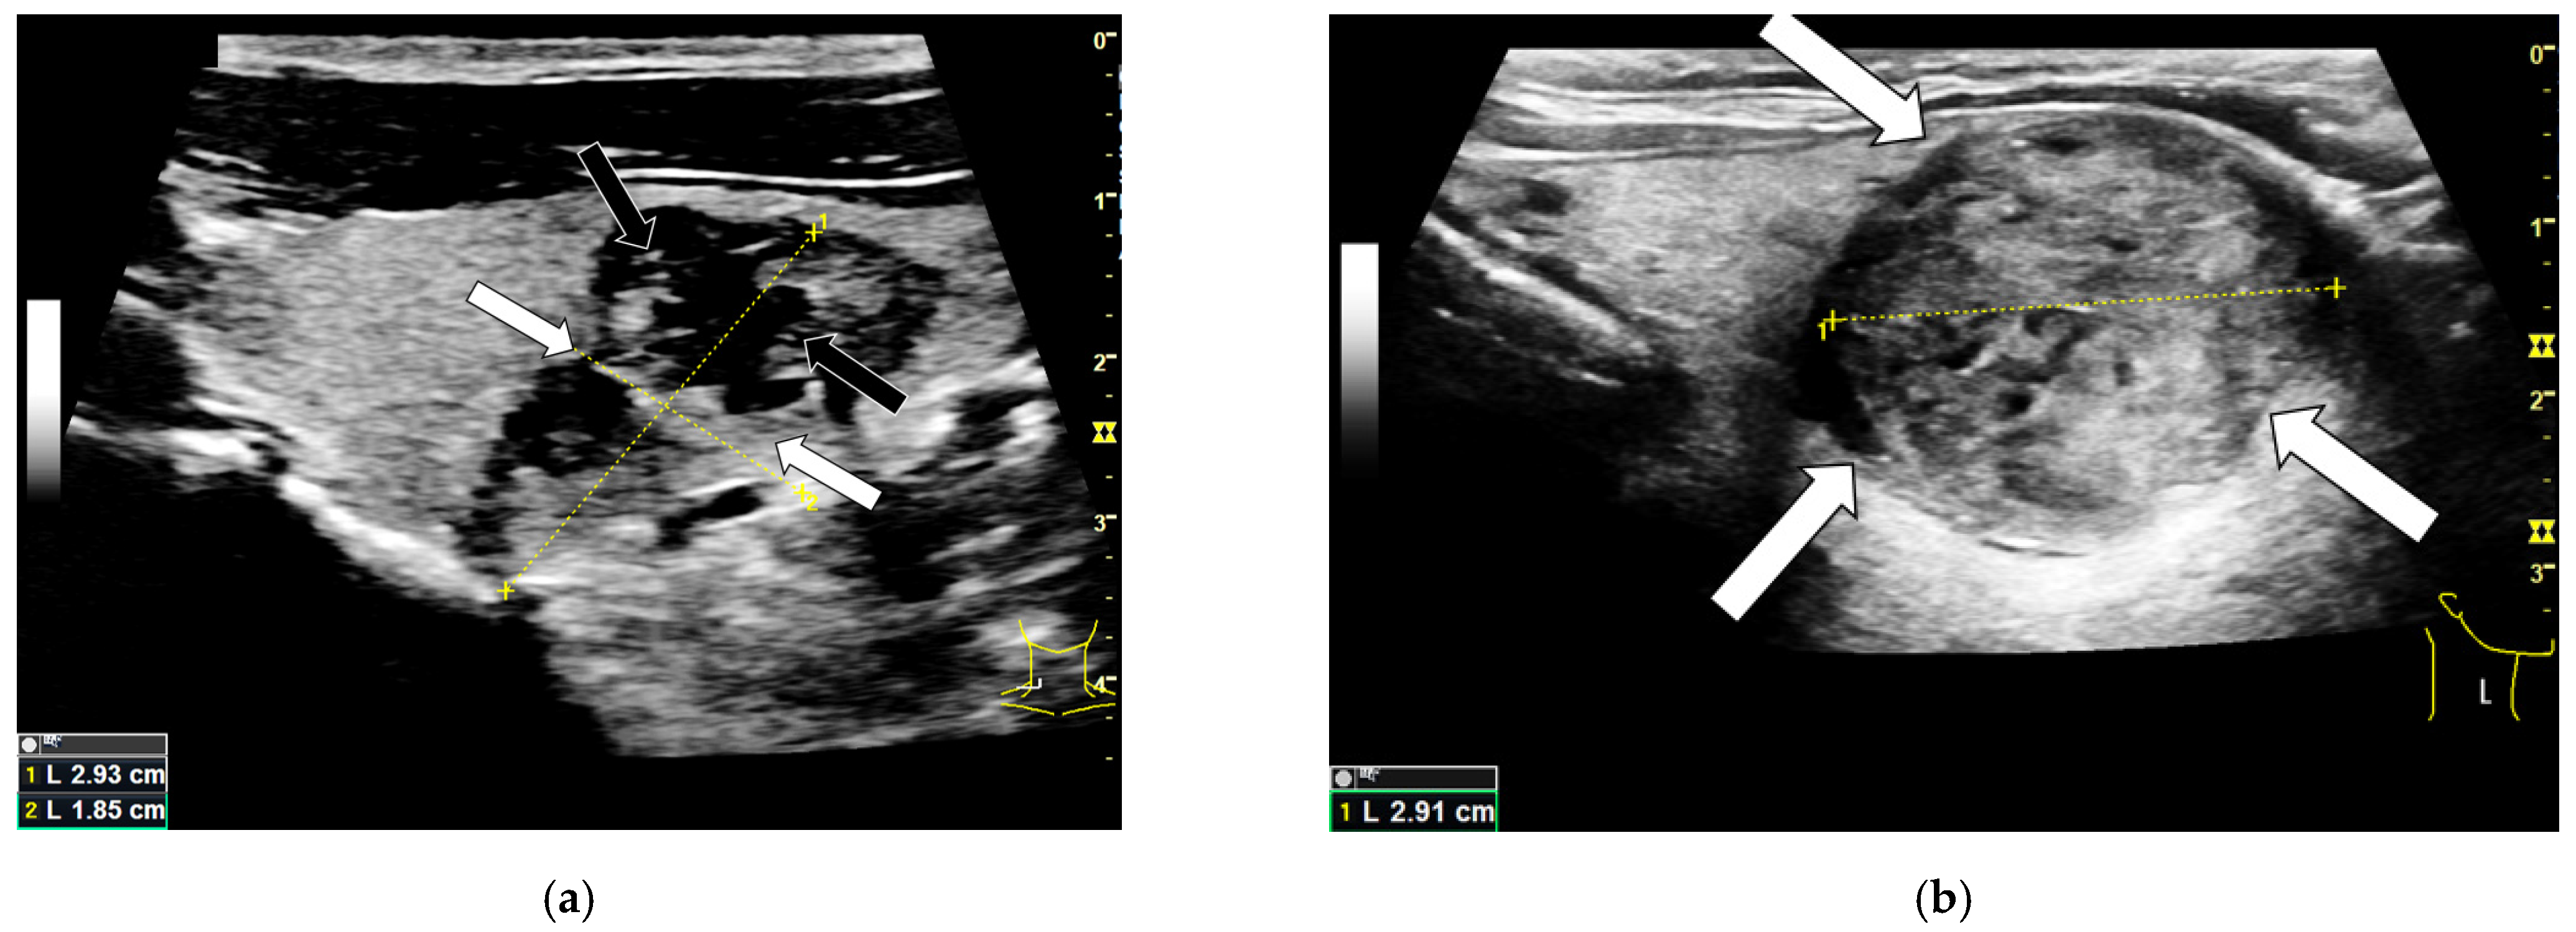

3.1. B-Mode Findings

3.2. Shear-Wave Elastography